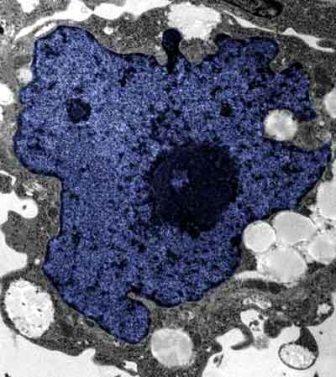

在成人體內及胚胎內發現的干細胞屬于主細胞,能發育成各種各樣的組織,可作為人體“修補工具箱”,取代死去及腐壞細胞組織。此前,最可行的干細胞為胚胎干細胞,但它的使用一直受到爭議,因為要在胚胎抽取干細胞會令胚胎死亡,有人認為這樣是變相奪走一條生命。

2007年,日本京都大學教授山中伸彌為首的科研小組證明,利用病毒倒撥普通皮膚細胞的“生理時鐘”,可把它們變成像胚胎干細胞那樣具備“變身”能力的細胞。但利用病毒把基因輸入細胞,有可能導致癌癥。這即是說使用這些細胞的風險很大。

來自英國和加拿大的兩組研究員所用的新方法不必使用病毒。這項新突破暗示科學家現在能更認真地看待在醫學中利用皮膚干細胞(即誘導多功能干細胞,俗稱“iPs”細胞)的前景。

這些細胞只要配以適當的化學品和蛋白質,就能轉化成腦神經元、制造胰島素的胰腺細胞、骨或軟骨、心臟肌肉,或其它多種組織。這些細胞利用病人皮膚來培育,更暗示它們不會被人體排斥。